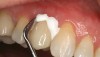

(10.) When preparing to seat a crown where mostly dentin is present, the self-etch technique is well-suited to provide high bond strength.

Figure 10

Bonding the Surface of the Tooth

When preparing a tooth to receive a bonded ceramic restoration, a proper bonding protocol must be followed. If a large amount of enamel is present, an etch-and-rinse technique with phosphoric acid followed by an application of primer/adhesive is the preferred method. These situations include those involving inlays, onlays, and veneers. In most bonding situations where a full-coverage restoration is indicated, self-etching adhesive systems have been shown to work extremely well (Figure 10). This is because the entire preparation is now in dentin, where self-etching adhesives have the strongest microtensile bond strengths.11,12